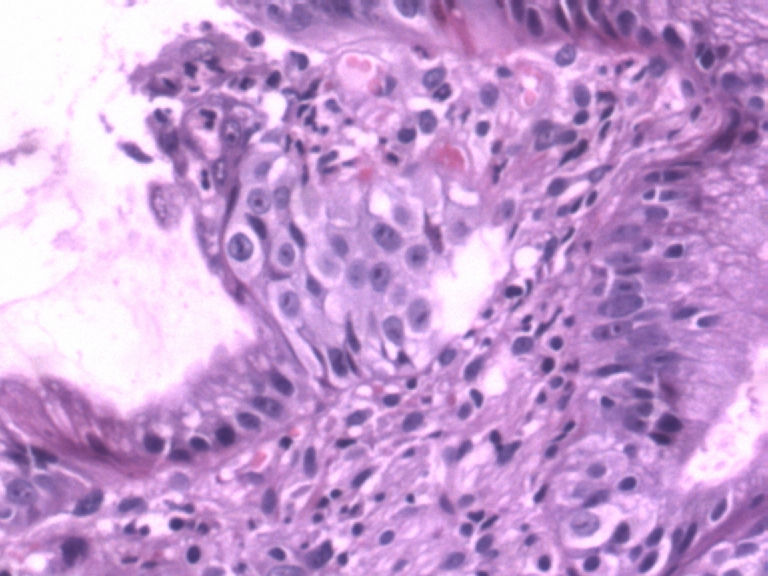

男,50岁,胃镜活检食管下段溃疡组织3块。

• 胃镜活检食管下段溃疡组织3块图1

图1

2图、3、4图上似乎有核分裂.可视为不典型增生。

请教一下2图、3、4图上似乎有核分裂如何看待? 学习了!谢谢各位老师!

从图片看,应该是贲门部位的组织,显示急性炎症改变,腺体结构稍有不规则,可能为炎性刺激所致,总之未见肿瘤性病变。

图示急性炎症,炎症累及上皮,腺细胞反应性增生。

胃镜取材部位距门齿多少厘米?没有看到鳞状上皮,是贲门或者胃食管交界处吧?

结构很重要,请给几张低倍图。从现有的图看不够癌。

多传几个低倍图,是不是取的贲门粘膜?这几个腺体有问题,镜下有没有鳞状上皮?等待上传图片。